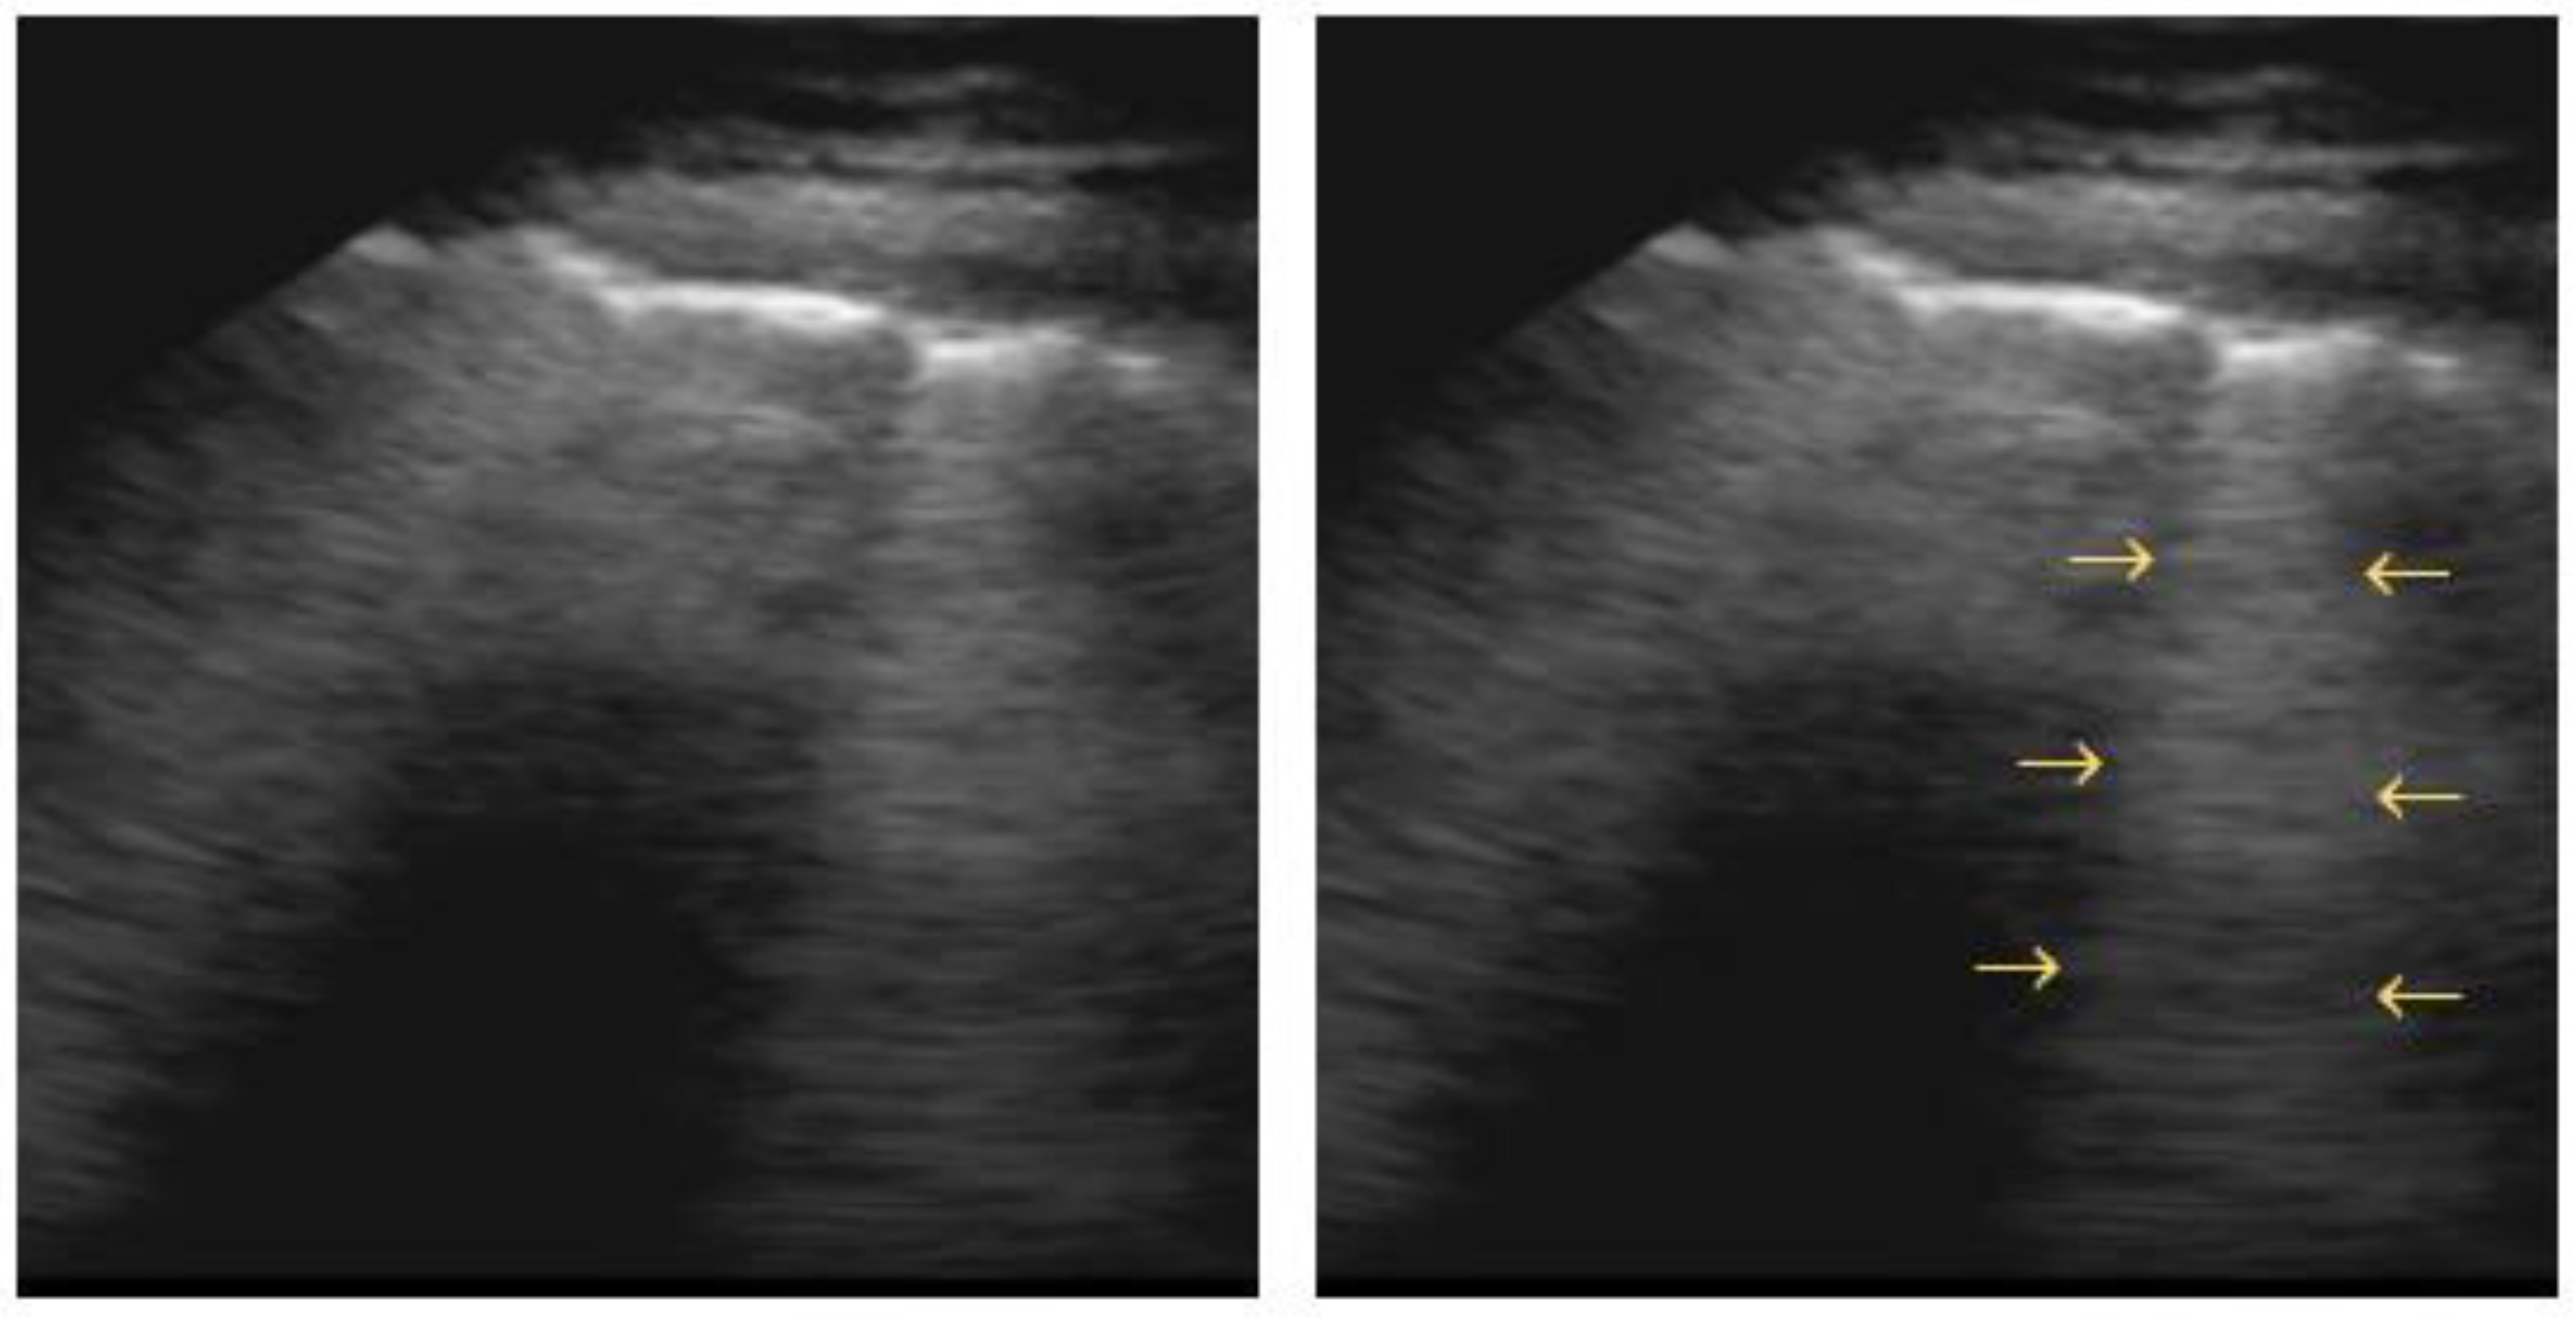

4.3. Lung Consolidation

- Bouhemad, B.; Zhang, M.; Lu, Q.; Rouby, J.J. Clinical Review: Bedside Lung Ultrasound in Critical Care Practice. Crit. Care 2007, 11, 205. [Google Scholar] [CrossRef]

- Lee, K.S.; Han, J.; Chung, M.P.; Jeong, Y.J. Consolidation. In Radiology Illustrated: Chest Radiology; Springer: Berlin/Heidelberg, Germany, 2014; pp. 221–233. [Google Scholar] [CrossRef]

- Gehmacher, O.; Mathis, G.; Kopf, A.; Scheier, M. Ultrasound Imaging of Pneumonia. Ultrasound Med. Biol. 1995, 21, 1119–1122. [Google Scholar] [CrossRef]

- Lichtenstein, D.; Mezière, G.; Seitz, J. The Dynamic Air Bronchogram. A Lung Ultrasound Sign of Alveolar Consolidation Ruling out Atelectasis. Chest 2009, 135, 1421–1425. [Google Scholar] [CrossRef] [PubMed]

- Cortellaro, F.; Colombo, S.; Coen, D.; Duca, P.G. Lung Ultrasound Is an Accurate Diagnostic Tool for the Diagnosis of Pneumonia in the Emergency Department. Emerg. Med. J. 2012, 29, 19–23. [Google Scholar] [CrossRef]

- Reissig, A.; Copetti, R.; Mathis, G.; Mempel, C.; Schuler, A.; Zechner, P.; Aliberti, S.; Neumann, R.; Kroegel, C.; Hoyer, H. Lung Ultrasound in the Diagnosis and Follow-up of Community-Acquired Pneumonia: A Prospective, Multicenter, Diagnostic Accuracy Study. Chest 2012, 142, 965–972. [Google Scholar] [CrossRef]

- Mongodi, S.; Via, G.; Girard, M.; Rouquette, I.; Misset, B.; Braschi, A.; Mojoli, F.; Bouhemad, B. Lung Ultrasound for Early Diagnosis of Ventilator-Associated Pneumonia. Chest 2016, 149, 969–980. [Google Scholar] [CrossRef]